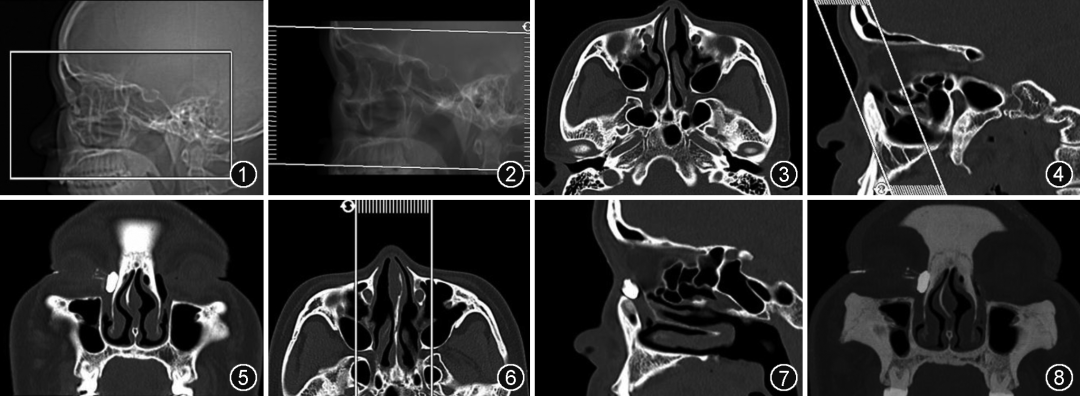

1. 扫描体位和范围:采用仰卧位,听眶下线与床面垂直,正中矢状面与床面中线重合。扫描基线为听眶下线,扫描范围从眼眶上缘至上颌骨下缘 (证据级别高,强推荐),见图1。

1. 多平面重组(multiplane reformation,MPR):包括横断面、冠状面和矢状面(表 2,图 2~7),在骨算法薄层图像上完成。

图1 CT泪道造影扫描范围示意图。扫描范围从眼眶上缘至上颌骨下缘

图2~7 CT泪道造影多平面重组基线和范围。图2为横断面重组基线和范围,图3为泪道横断面图像。图4为冠状面重组基线和范围,图5为泪道冠状面图像。图6为矢状面重组基线和范围,图7为泪道矢状面图像

图8 CT泪道造影冠状面最大密度投影图像。范围包含鼻泪管前后缘

2.最大密度投影(maximum intensity projection, MIP)重组:在冠状面重组图像基础上进行 MIP 重组(图8)。